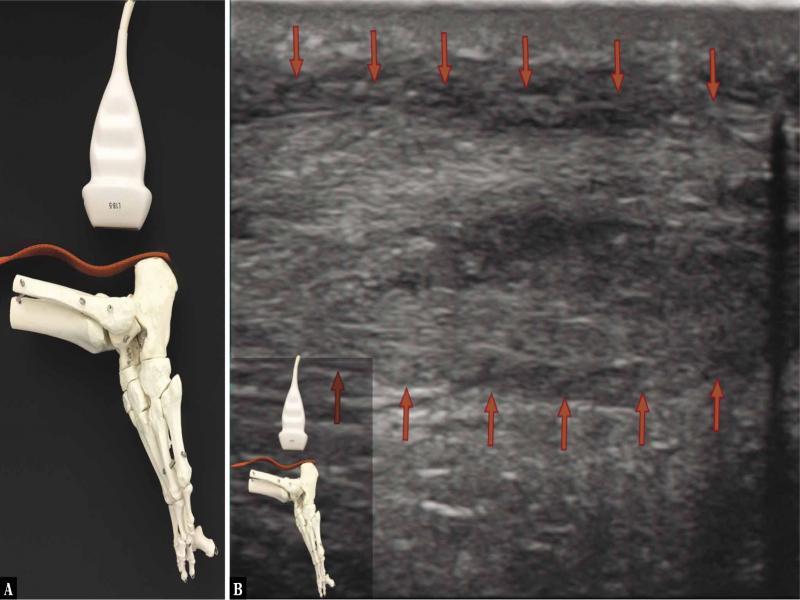

Fig. 5.

![Ultrasound examination protocol. A. The transducer is placed longitudinally above the calcaneal tuberosity, along the AT; active maximum plantar flexion of the ankle joint [curved arrow] with the diagnostician’s hand applying ground-like foot resistance [straight arrow] as in the heel-rise test. No tension is seen in the AT, which is undulated. The heel-rise movement is performed not by the force of the triceps surae muscle, but with the strength of the other plantar flexors. The image indicates a dysfunction of the surgically treated AT, healing with elongation of the tendon. B. A longitudinal 18–5 MHz US image of the AT, the evident fibrillar structure, but the tendon fibres appear undulated in the dynamic imaging [the curved red lines indicate the wavy course of the fibres], indicating the lack of tension; the tendon is loose [red arrows mark the borders of the tendon]](https://sciendo-parsed.s3.eu-central-1.amazonaws.com/64722e23215d2f6c89dbec00/j_jou.2021.0043_fig_006.jpg?X-Amz-Algorithm=AWS4-HMAC-SHA256&X-Amz-Content-Sha256=UNSIGNED-PAYLOAD&X-Amz-Credential=ASIA6AP2G7AKBY2AOJTK%2F20251216%2Feu-central-1%2Fs3%2Faws4_request&X-Amz-Date=20251216T170210Z&X-Amz-Expires=3600&X-Amz-Security-Token=IQoJb3JpZ2luX2VjEJ%2F%2F%2F%2F%2F%2F%2F%2F%2F%2F%2FwEaDGV1LWNlbnRyYWwtMSJIMEYCIQDpGWJy5nYmL6vQIHHt%2BcL%2F3OSMUmRuP2Jq%2F0ZR1%2FLQBwIhAMOCdMyV4r3yYa%2BF%2FudRVaQIR4fmJylEiwzwqN7lTdT5KrwFCGgQAhoMOTYzMTM0Mjg5OTQwIgz4VpTpHrGQ%2BRwhfVIqmQUmdJgnr7B%2F2TCxvDKqjEoGFRsgxmY1WO7B2uHZlmD80cdU17oWnLhWozEmhOcl3%2FA2q7bDkKBAuPcFO1a7dNHauScY2SzHlX0kIwGWBTyagWuMSXxWSKl7tuRn79BzKKKgACwrvnuaElPejVfsbXCLbokYmV3F5d6L7ZvYrBqtQi69XC21CoAlb8Y6i6%2FgGjbHb96ZBwCqvP7cOXSUTpBBNcWXDb3SBoKgMOvVGHUg3rSkHFBWbeUJWEqFQuQLNZGIPzAiqdGcNpaQoxwYfz5gf2hRAObi1TmBBQCJk0SxpwaFBWoacduWkTQZ5HNbLbV2Y7aFE3mDRSzYCiCfLMQh7Mgepw0nBxMmfE85hi32y%2BHl0YbHclUDfuc6cLW%2FYcTSrFNW5DY1zlMhrYkTdcHwhlV1hhIJTQNjAopybRxyhl8UYT%2FarnBEwsCeDtNSkjr%2BbyoA4Mb304CzPuGRdqK9emQVbV5UYjlPpV4HDHxB%2Feh%2FvM4JIZO4n8g6cp3NqtH4DmY0IW9MSRtklWQp1NGIx%2FvKjGOq7aOzqrJapYKvKLlD5e4RXY6v%2FiOPFbAdlTfn5%2FqC4BWLoxMGssJ9k0H38JHeskVYSwPhVqIo0EtaUeEaKSM06dRorQWA4zp9F2C8ovAo54ubZDzgUdOR0AQTvRjPzuFLiqLDfhn7QV8H0gLPqSM190VJgPIW5IZZPui4U7%2FBneLPSyQBM0j6QtUb8Mst%2FeYnWZLJMIdEPA%2Bv6au%2BzISiEhwEeyP69vVeq%2B5DRurxZDk6yvkPWt7OPS0VcMYYkMEE%2FBKpoOMCHV5smh95YG7YQar4J%2FuRfCRSBakAngbpy9rbUzTx0nincY30w2DOtdkRQ%2B6llm11f5dKO2lDvaYDR9zwsjDY3YXKBjqwAWriJvfX%2BElci0gwZQievDMAbkmHC4QI%2FqxewR1beknZpaCkRtCONkVDPkjy%2BT4qSFomaXZUpQZ4%2FUCmLMIxbgvXVx2C%2F8RvVqLErXggh0KomRU%2B0YjqHSFLW6f4wXhBudqG47DjGNdcJofTT2PytMHHltz%2Fhgs2cVWnTfkhMiVrxvUgXovn9cYHmefQfFeOjU7b7EZJzwNBhn624LDbKUNBrlDn2%2FKsMwkUHsc1t%2Flz&X-Amz-Signature=5c058dfc8d57db71cc8c56e105f3f966c3ffbf4d08837e250f3c565e15ac09ea&X-Amz-SignedHeaders=host&x-amz-checksum-mode=ENABLED&x-id=GetObject)